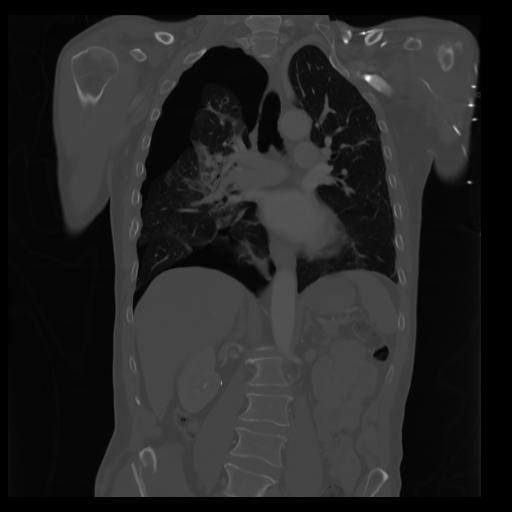

29 CUERPO,CE,Coronal,3.000,CUERPO,Coronal,